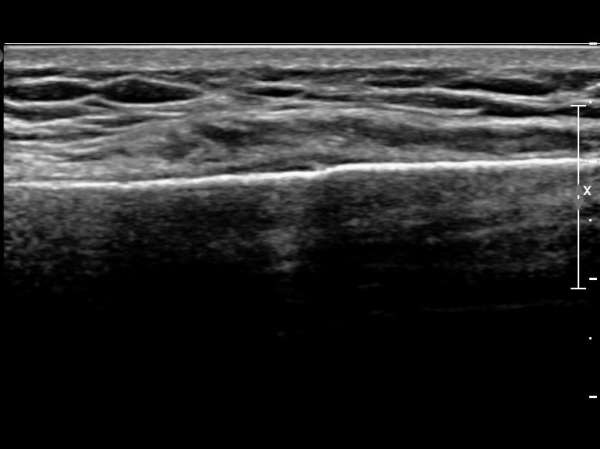

ŽÃËÀÚ¸¦ ¾à°£ ¸»´ÜÀ¸·Î À̵¿ÇÏ´Ï ¿¬ºÎÁ¶Á÷ ºÎÁ¾ÀÌ ´õ¿í ½ÉÇÏ°Ô °üÂûµÇ°í(»çÁø 2),

Á¶±Ý ´õ ¸»´ÜÀ¸·Î À̵¿ÇÏ´Ï Äá¾Ë»À ÇÇÁú°ñ ¿¬¼Ó¼º ¼Ò½ÇÀÌ °üÂûµÊ(»çÁö 3),